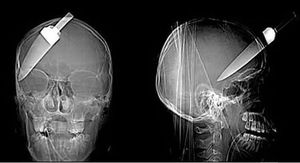

coltello

Conficcato

Testa